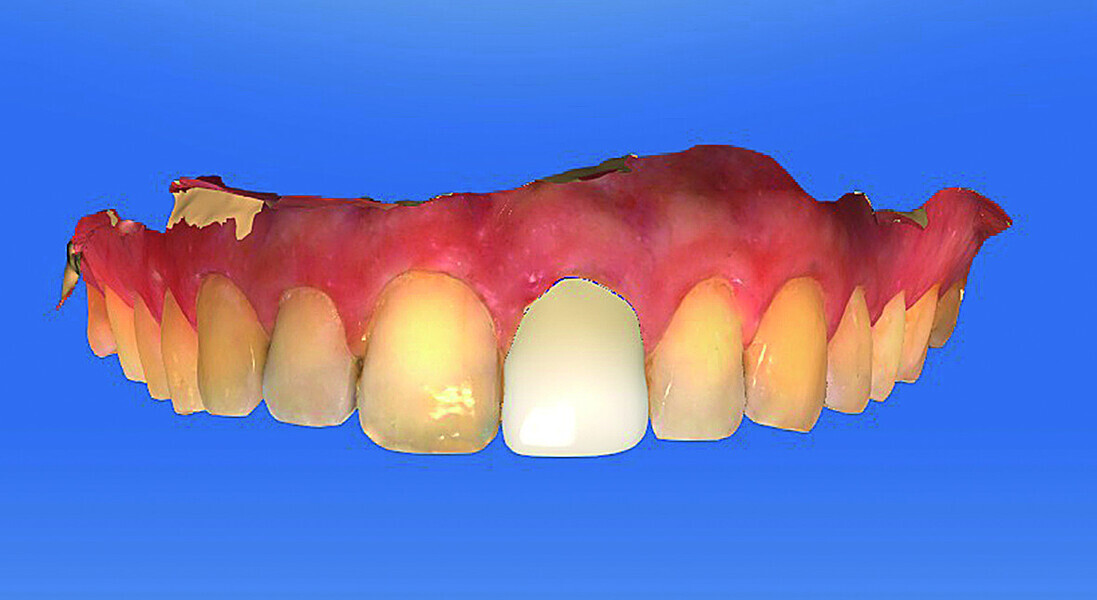

Fig. 12: The screw-retained crown as a finished polished temporary.